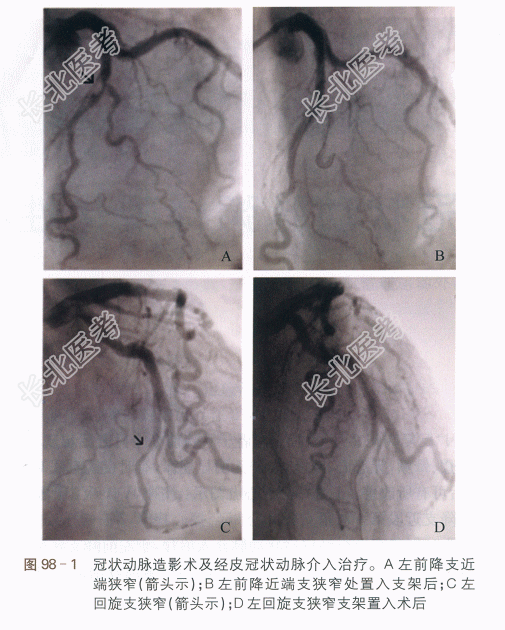

(3)冠脉造影(入院第2日):左主干(-),左前降支近中段支架通畅无再狭窄,远段50%局限狭窄;回旋支中段90%狭窄;右冠状动脉中段40%狭窄,如图98-1所示。

(入院第2日):左主干(-),左前降支近中段支架通畅无再狭窄,远段50%局限狭窄;回旋支中段90%狭窄;右冠状动脉中段40%狭窄。于回旋支狭窄处置入Endeavor Resolute 2.75mm×18mm进口药物支架1枚(见图98-1D)。